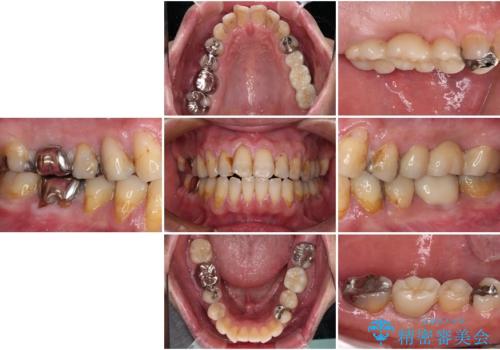

欠損と痛み 奥歯のむし歯治療

- 根っこの一部だけになった歯と咬むと痛みのある歯を気にして来院された患者様です。

上顎の歯根のみとなった歯は抜歯が必要であったので、抜歯を行い、インプラントあるいはブリッジのよる補綴治療を提案しました。

前後の歯は銀歯が装着されていたため、ブリッジによる補綴治療として、前後の歯もセラミックに置き換えることとしました。

下顎の根管治療がされた大臼歯は咬合時に痛みが認められたため、再度根管治療を行った後に補綴治療することとしました。

歯根のみとなっていた上顎の歯は、そのうち治療すれば残せるであろうと思っていたようですが、どこの歯医者に相談しても抜歯と言われたため、抜歯することとしたようです。

むし歯は放置して改善することはあり得ませんので、早めの処置が大切です。